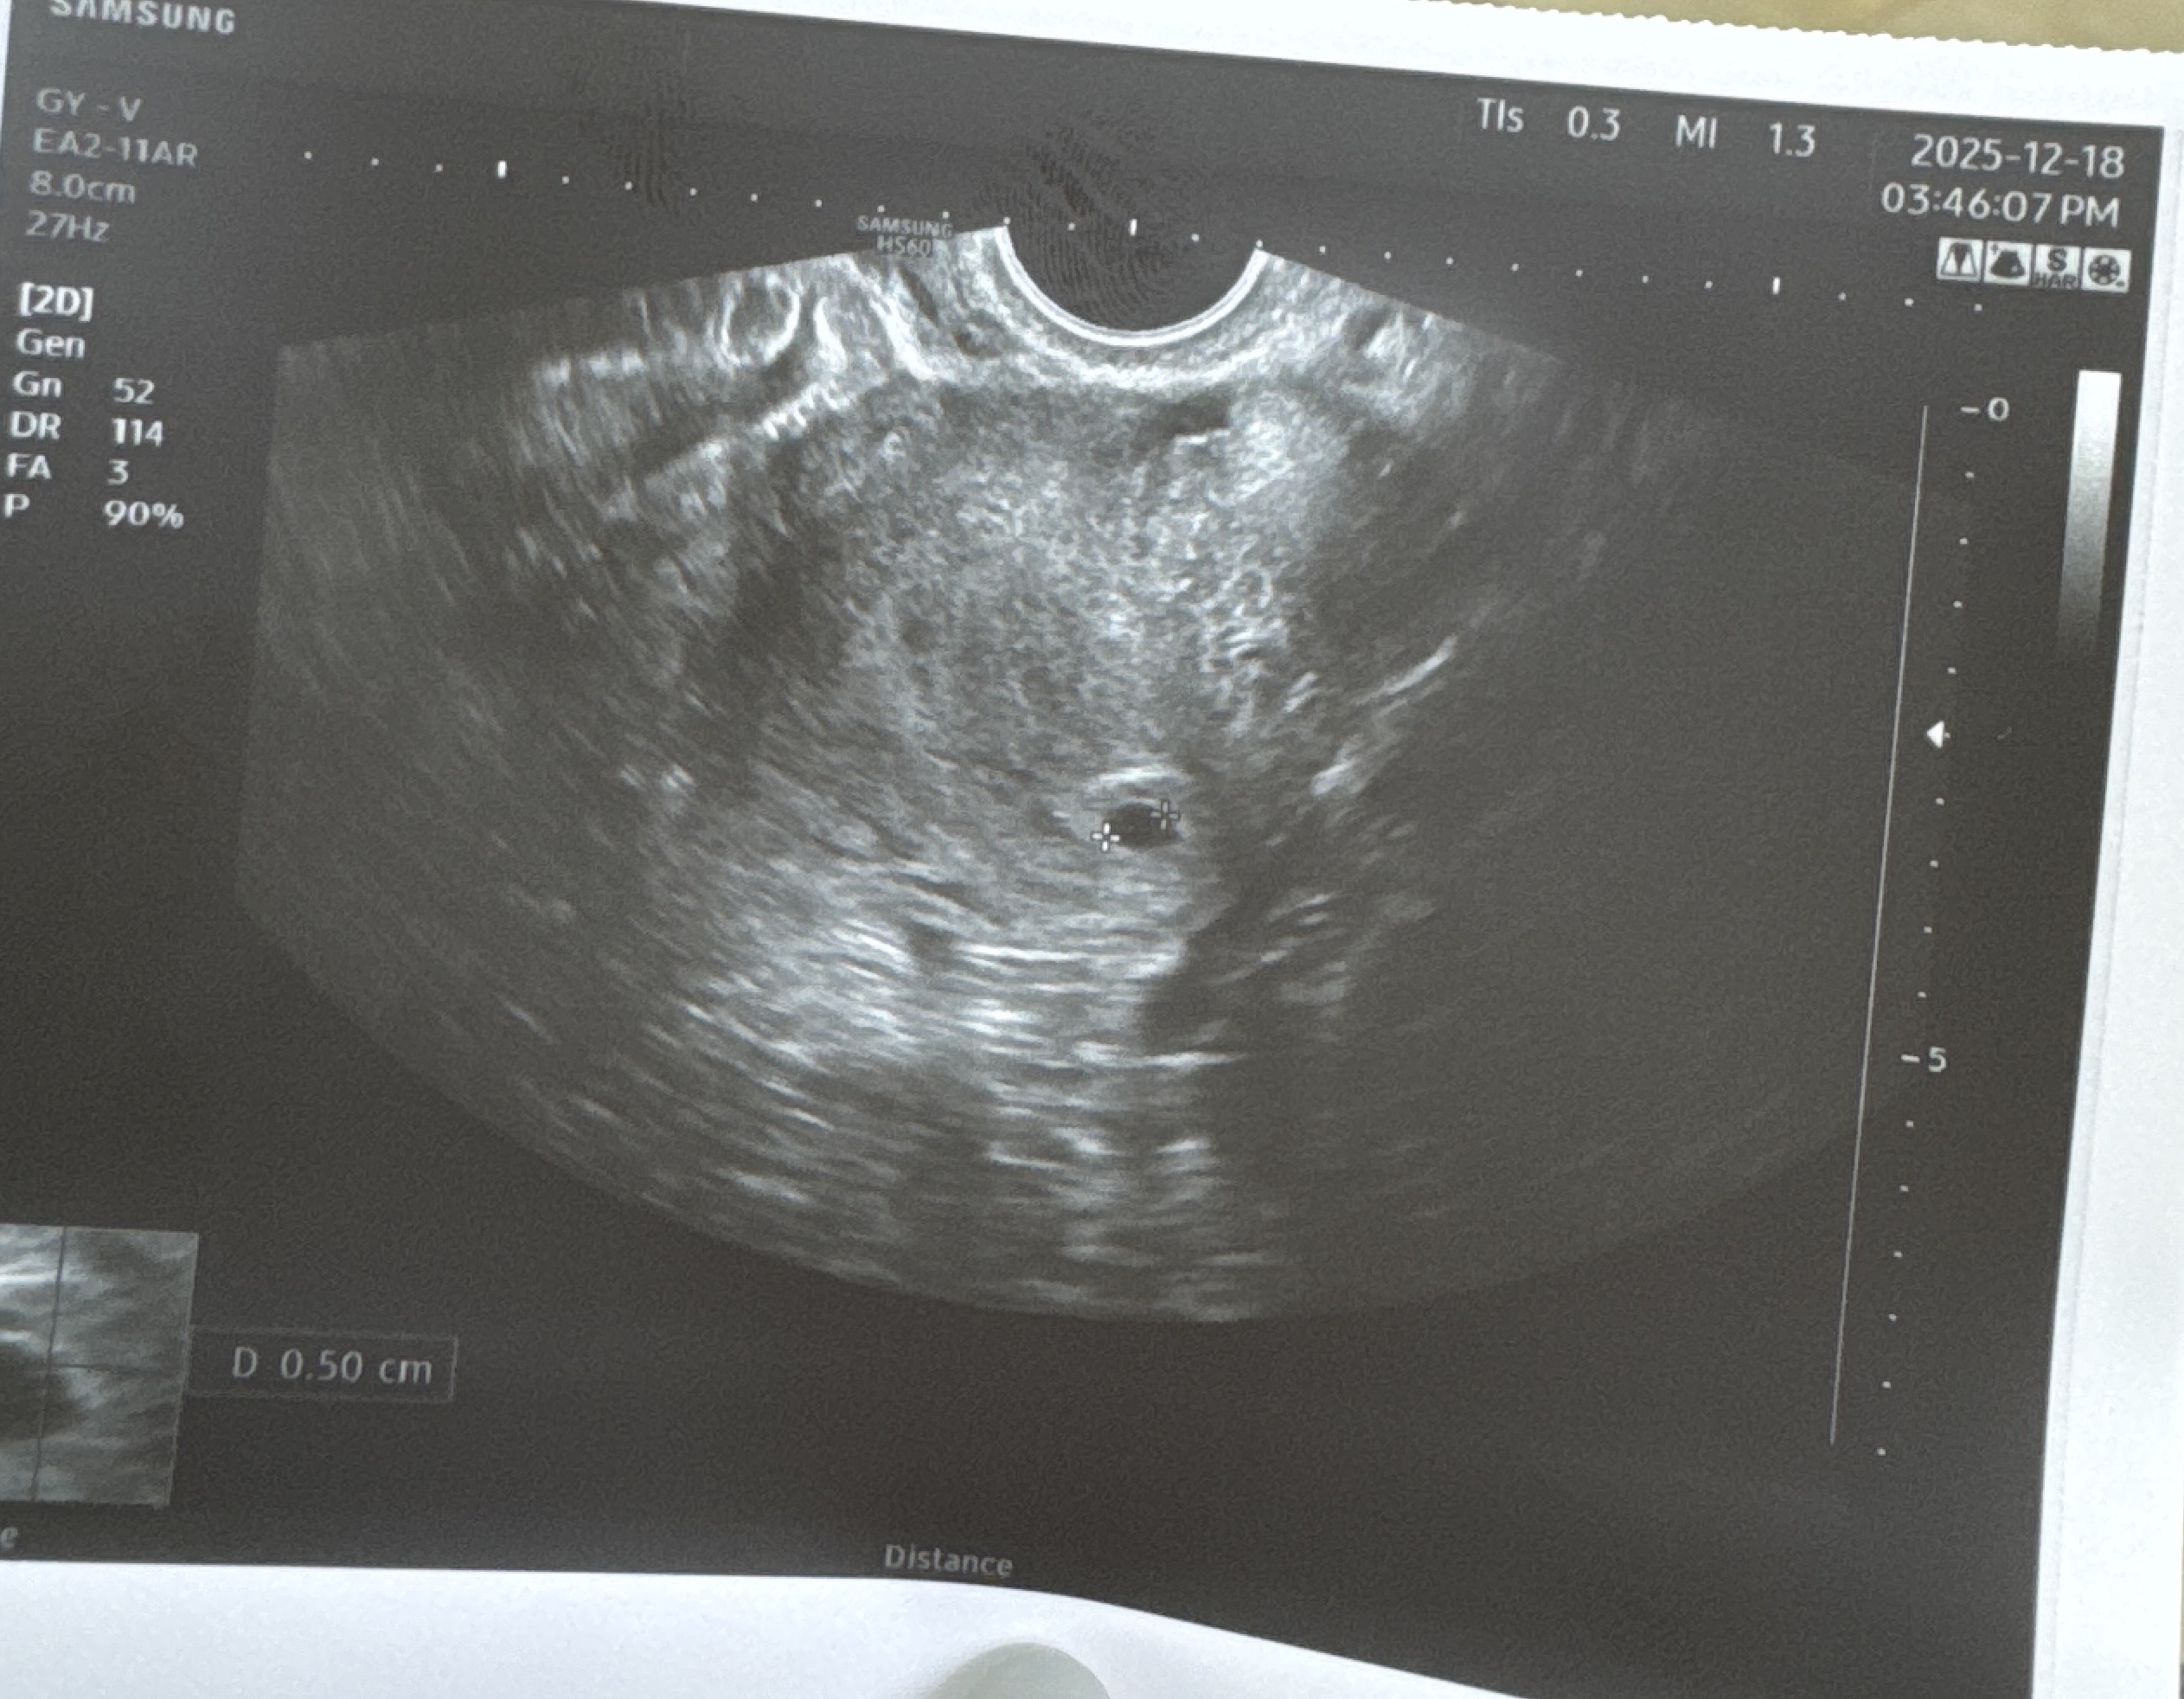

5주차 3일 난황이 안보여요

제목 그대로 5주차3일에 아기집만 확인하고 난황은 다음주쯤에 보자는데 이때 안보이는 경우가 많은가요? 입덧도 안하는거같은데.. 없는분들도 계신가요??